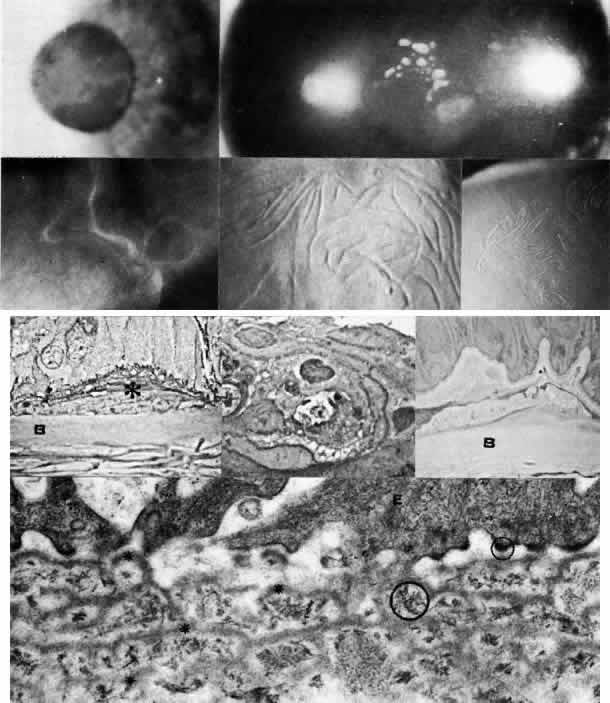

Fig. 3. Peters' anomaly. Schematic drawing of ocular features. Top left. Clinical photo of typical bilateral Peters' anomaly with large, dense central leukomata, which was successfully treated by penetrating keratoplasty with optical iridectomy of the fellow eye. Top center. Intraoperative photo demonstrates adhesion of the lens to the posterior cornea as a corneal button (grasped with forceps) is trephined. Top right. Successful penetrating keratoplasty of a patient with bilateral Peters' anomaly. Bottom, upper left. Survey light photomicrograph of a corneal button from the case illustrated clinically (top center) shows termination of Bowman's membrane (at arrowhead) corresponding to the area of adhesion between the posterior cornea and lens (L). Descemet's membrane, present peripherally, terminates centrally in a layer of retrocorneal fibrous tissue (*) interposed between the lens and stroma. Direct contact between the retrocorneal fibrous tissue and continuous lens capsule is evident (paraphenylenediamine, phase contrast, × 60). Bottom, lower left. Phase-contrast micrograph of posterior cornea adjacent to a central stromal defect shows termination (at arrowhead) of undulating Descemet's membrane between the stroma and retrocorneal fibrous tissue (paraphenylenediamine, × 400). Bottom right. Transmission electron micrograph of posterior cornea shows attenuated keratocytes (K) with phagocytic contents, disorganized posterior stromal lamellae, and markedly thin and multilaminar Descemet's membrane (DM) with attenuated but continuous endothelium (E). AC, anterior chamber. (x 7000) (Schematic. Grayson M: Diseases of the Cornea, p 29. St. Louis, CV Mosby, 1979)

Histopathologic changes are present in all layers of the cornea in Peters' anomaly.19,20,38–41 Often the anterior changes, which include disorganization of epithelium, fibrovascular pannus, and loss of Bowman's layer due to long-standing edema, are secondary to the posterior abnormalities. Fluid lakes are also present in the affected stroma.

In the peripheral and unaffected areas, the corneal endothelium forms a continuous monolayer, and Descemet's membrane is of normal, uniform thickness (approximately 5μm). In the area of defect, however, endothelium and Descemet's membrane can terminate abruptly or be severely attenuated. The affected Descemet's membrane is composed of multiple laminations of basement membrane-like material, with interspersed collagen fibrils and fine filaments. Since such abnormal material is elaborated by the corneal endothelium, a fibroblastic metaplasia of the endotheliogenic mesenchyme is likely, as is thought to occur in a number of corneal conditions in which the endothelium is similarly disturbed to secrete a posterior collagen layer.42,43

The lens abnormalities in Peters' anomaly are characterized histologically by a stalklike connection between the lens and the posterior corneal defect, suggesting primary incomplete separation of the lens vesicle. Alternatively, there may be contact of a morphologically intact lens to the posterior cornea, suggesting subsequent anterior displacement of a normally developed lens.

There are several reasonable explanations for a central corneal leukoma of the Peters' variety. One is incomplete central migration of corneogenic mesenchyme (i.e., neural crest cells), accounting for posterior endothelial and stromal defects.23 This is corroborated by the finding of abnormally large stromal collagen fibrils of 36 to 60 nm in some patients with Peters' anomaly. A similar abnormality of mesenchymal development is found also in sclerocornea and congenital hereditary endothelial dystrophy.22 Another explanation of posterior corneal leukoma of a Peters' type is an in utero subluxation of the lens, either prior to or after its full development, in either case interrupting the normal migration or function of the developing endothelium.